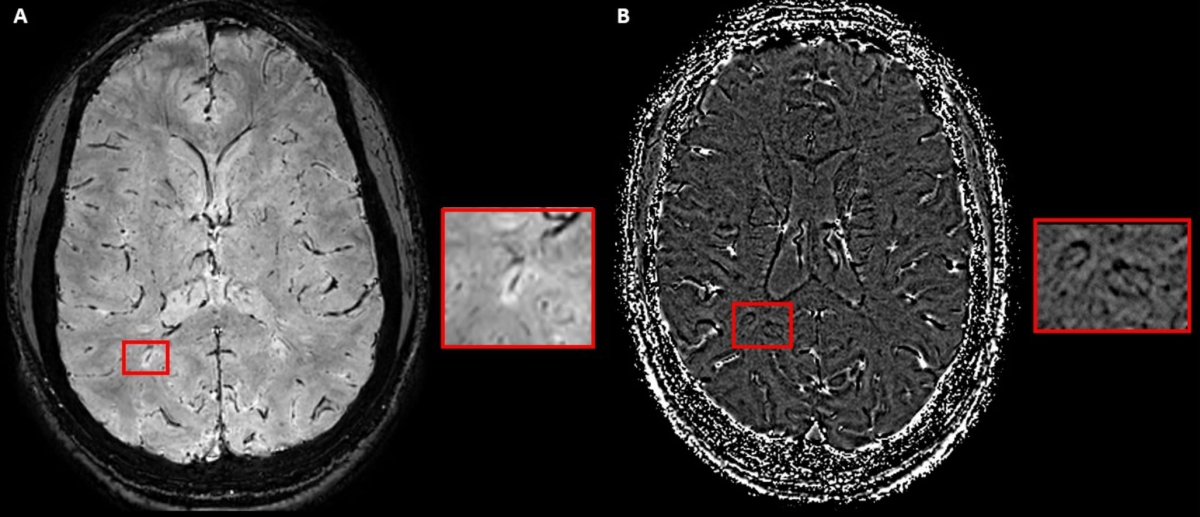

Schéma représentant la mise en évidence d’une veine centrale sur des séquences SWI-EPI en magnitude (A), et d’un PRL en phase (B).

Pour parfaire ces limites, la révision des critères de McDonald amène deux nouveaux biomarqueurs IRM : la veine centrale (CVS) et l’anneau paramagnétique (PRL). L’étude de ces biomarqueurs se fait sur des séquences SWI. Le consensus de la NAIMS rappelle les critères d’identification de la veine centrale : un hyposignal linéaire ou punctiforme, qui se situe au centre de la lésion, visible dans au moins 2 plans perpendiculaires, et ce, en absence de veines multiples. De même, le PRL (dont l’étude se fait sur les séquences de phase de la SWI) correspond à une couronne linéaire généralement de même signal que le cortex, au pourtour d’au moins 2/3 d’une lésion, visible sur au moins 2 plans, en l’absence d’injection de produit de contraste. Le rôle de ces biomarqueurs devient prépondérant dans la SEP. En effet, lorsque cliniquement un patient montre des symptômes typiques et qu’en imagerie sont retrouvées au moins 2 localisations de dissémination spatiale, alors la présence de six CVS est suffisante pour poser le diagnostic. Si une seule localisation est présente, alors six CVS et un critère de dissémination temporelle ou des anomalies dans le liquide cérébrospinal font le diagnostic. Notons également que la mise en évidence du CVS augmente la spécificité du diagnostic, mais que sa présence n’en est pas moins nécessaire.